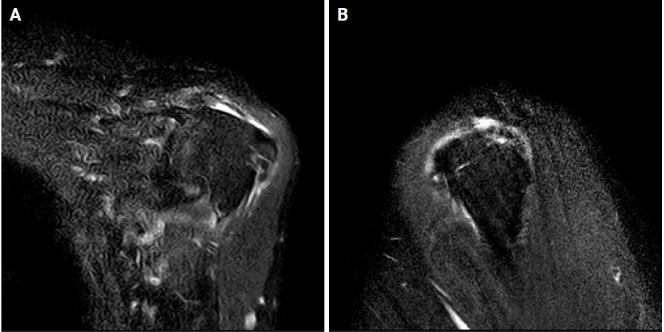

Acute postoperative parotitis, also known as anesthesia mumps, involves transient inflammation and enlargement of the parotid gland after general anesthesia. No case reports of acute postoperative parotitis after arthroscopic shoulder surgery have been reported to date. Therefore, we share our experience with a recent case of acute postoperative parotitis as a rare complication of arthroscopic rotator cuff repair in lateral decubitus position. Symptoms can be unilateral or bilateral, painless, and often resolve spontaneously within hours or days; in rare cases, such as upper airway obstruction, the condition can be fatal. Treatment options for parotitis vary from conservative to surgical depending on severity, and outcomes also vary. Therefore, orthopedic surgeons should be aware that this rare complication can occur after surgery, and patients should be warned before surgery.